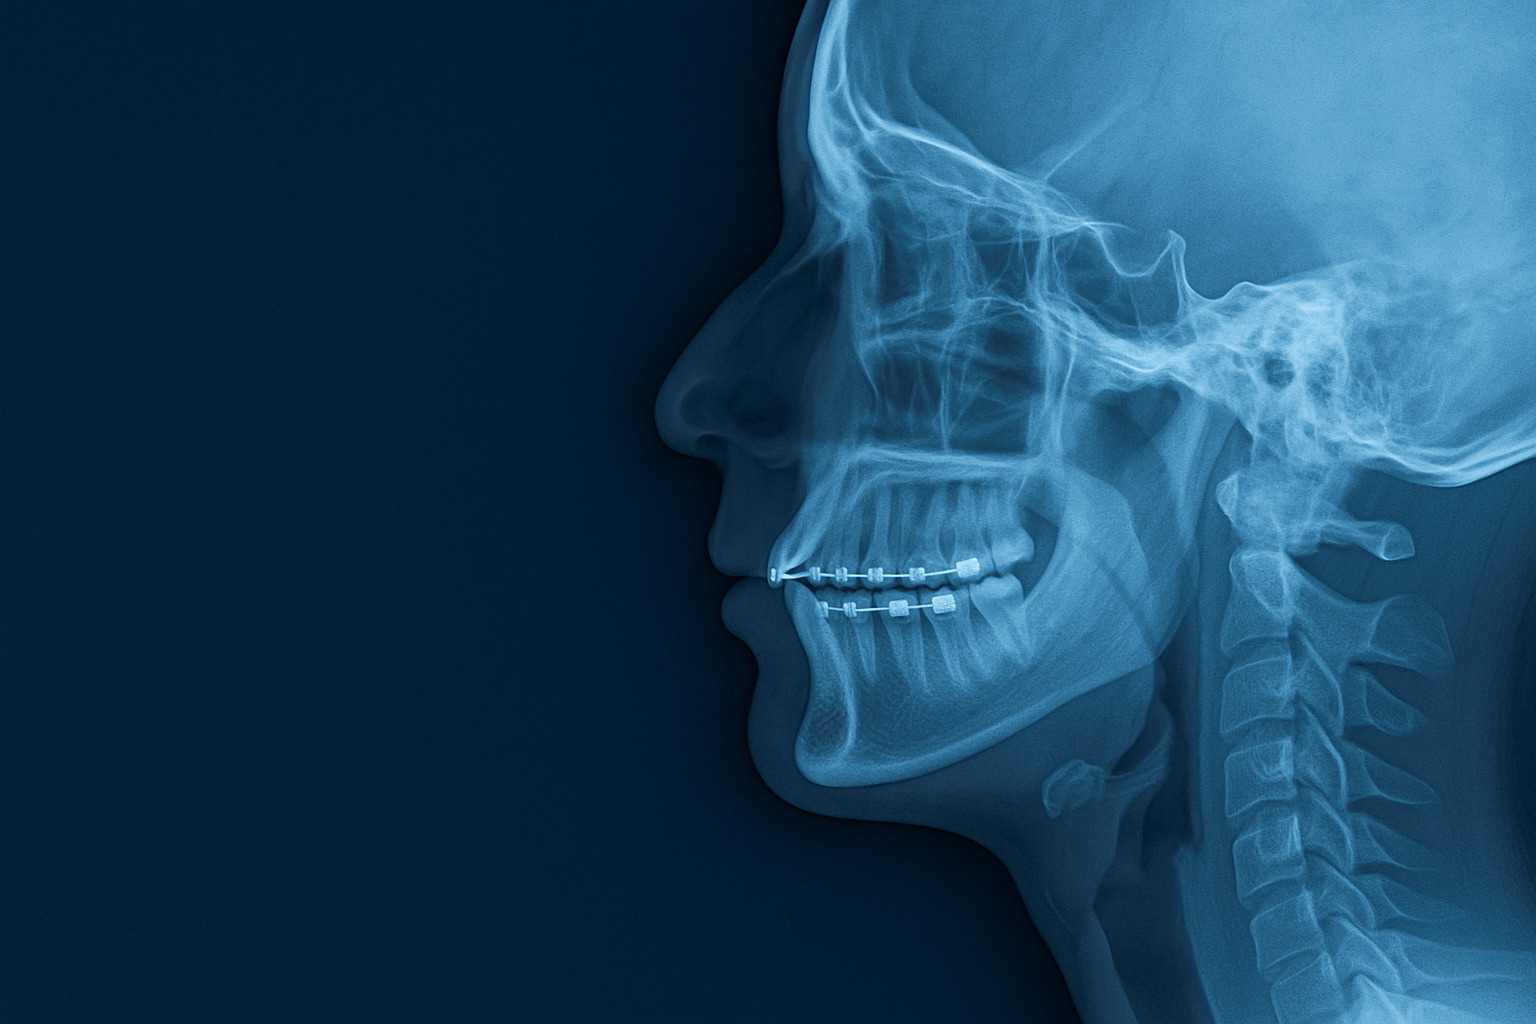

Lorsque les arcades dentaires sont trop étroites, l’air circule mal, la langue repose en position basse, et le nez devient sous-utilisé. Ce déséquilibre peut remonter jusqu’aux muscles cervicaux et provoquer une hypercompensation posturale.

Des appareils orthodontiques comme les expanseurs palatins ou les gouttières fonctionnelles peuvent améliorer cette situation en quelques mois.

Orthodontie et sommeil : la guerre contre l’apnée

L’apnée du sommeil n’est pas qu’un problème de ronflement. Elle réduit la qualité de vie, augmente les risques cardiovasculaires… et touche aussi des personnes jeunes, minces et sportives.

Certaines apnées sont causées par :

-

une mâchoire reculée,

un palais étroit,

une langue trop basse pendant le sommeil.

Les orthodontistes formés à l’orthopédie dento-faciale peuvent prescrire des appareils avancés qui repositionnent la mâchoire ou élargissent le palais, améliorant radicalement la qualité du sommeil.